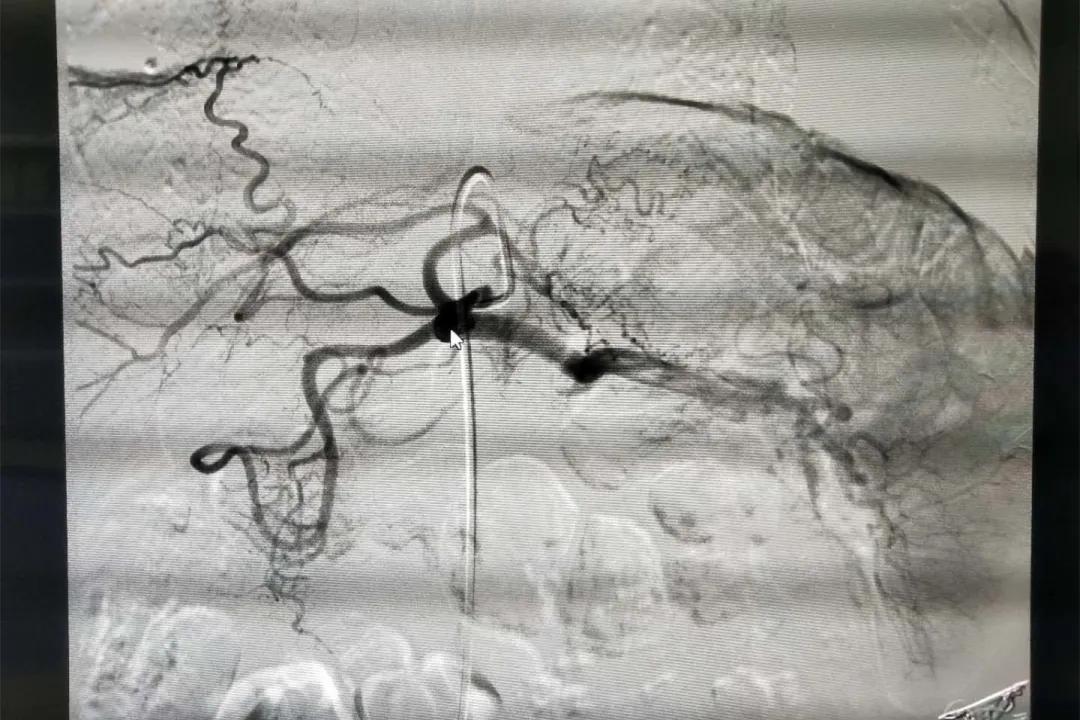

介入室里,宁阳县第一人民医院胸外科医生许彪和放射科介入科主任宁连金注视着眼前的屏幕,随着药物的注入,造影显示,肿瘤周围的末梢血运已经消失,严密观察之后,患者被送回病房。

许彪介绍说,肿瘤灌注化疗+栓塞治疗是运用DSA(数字减影技术)对患者肿瘤病灶进行精准定位,通过导管注射化疗药物,使药物直接作用于肿瘤细胞,对肿瘤组织进行破坏,杀死肿瘤细胞;同时,用药物阻断肿瘤的血液供应,使肿瘤组织无法再汲取营养,简单说,就是给肿瘤“断粮”,从而阻止肿瘤细胞的生长,甚至可以令其坏死凋亡,以达到控制肿瘤生长,使肿瘤缩小的目的。

放射介入科主任宁连金介绍说,DSA可视动脉介入灌注栓塞术是采用微创治疗的方式,仅在大腿根部处有一个2-3毫米的穿刺创口;将高浓度的药物直接作用于局部,发挥最大的抗肿瘤作用。而且对全身毒副作用小,能最大限度保护*体器人官**,绝大部分患者可耐受。适于多种肿瘤,如肝癌、肺癌、乳腺癌、胰腺癌、胃癌、肠癌、骨肉瘤等。